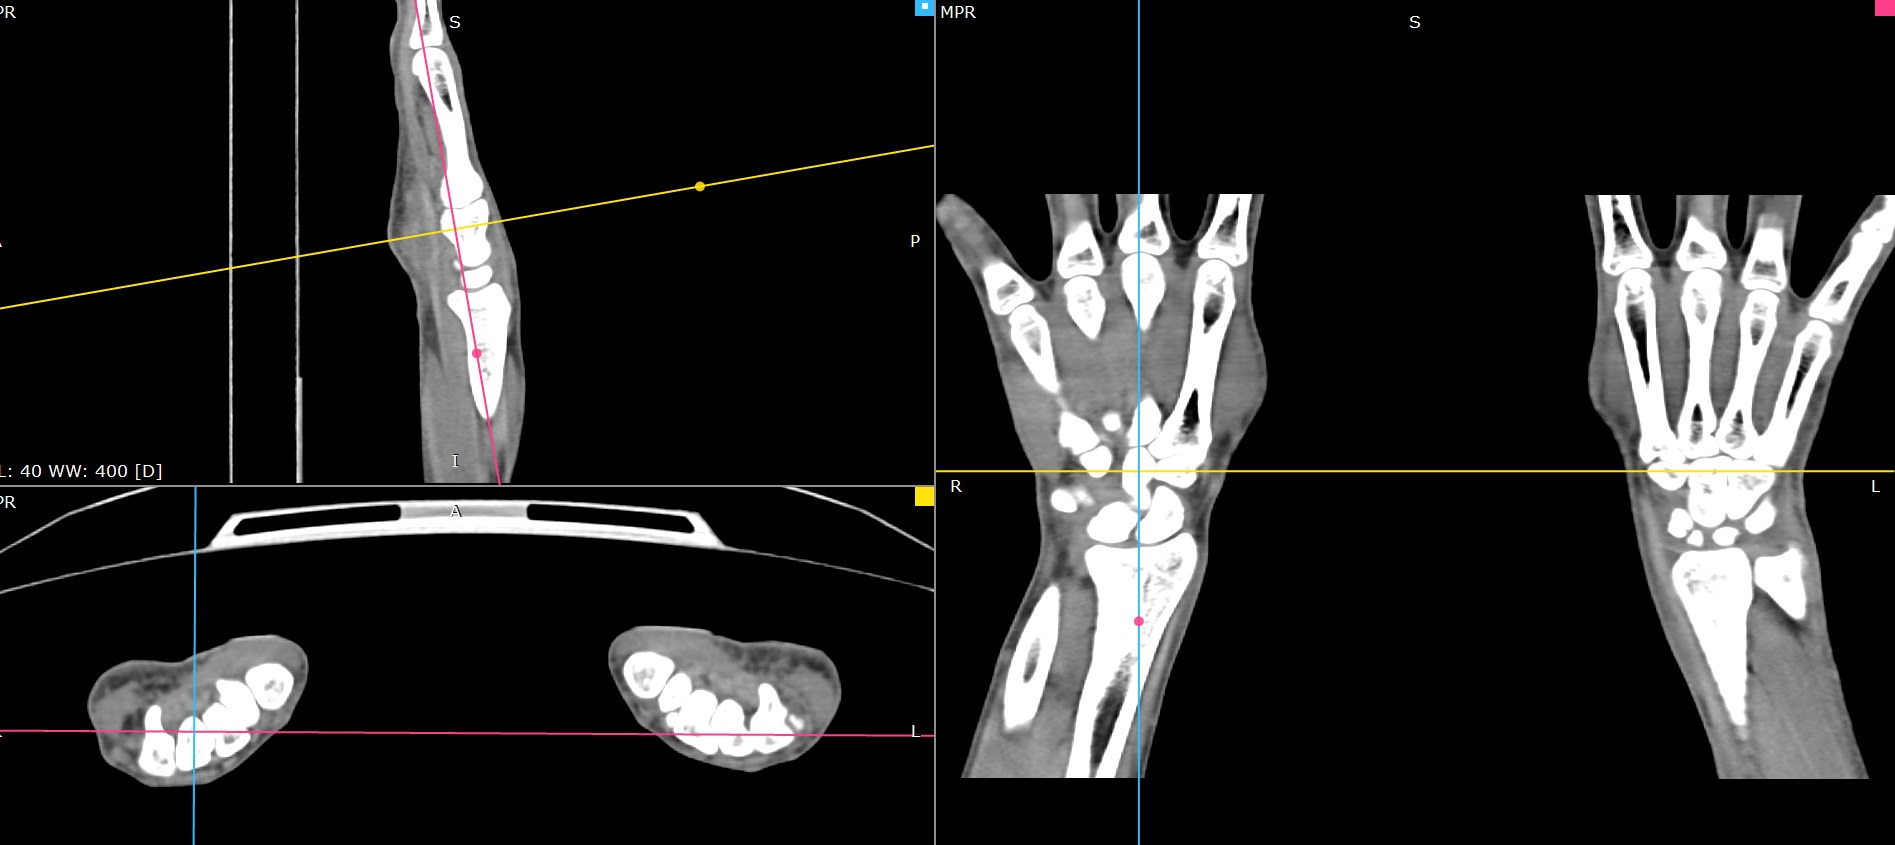

Мультиспиральная компьютерная томография является современным лучевым методом исследования, который позволяет с помощью рентгеновского излучения получить посрезовые снимки и после цифровой обработки создать объемные модели исследуемой области в мельчайших подробностях. Рентгеновские лучи в большей степени поглощаются плотными тканями организма, поэтому на снимках хорошо визуализируются кости скелета. Для более детальной оценки состояния мягкотканных структур зачастую проводится контрастное усиление.

В наших медицинских центрах КТ мягких тканей конечностей выполняется на современных мультиспиральных компьютерных томографах экспертного уровня TOSHIBA AQUILION. Аппараты послойно сканируют область исследования, одномоментно выполняя множество тончайших срезов. В результате получаются снимки высокого качества и трехмерные модели с изображением костного скелета и мягких тканей конечностей. При этом методика скоростного мультисрезового сканирования обеспечивает минимальную дозу рентгеновского облучения для пациента.